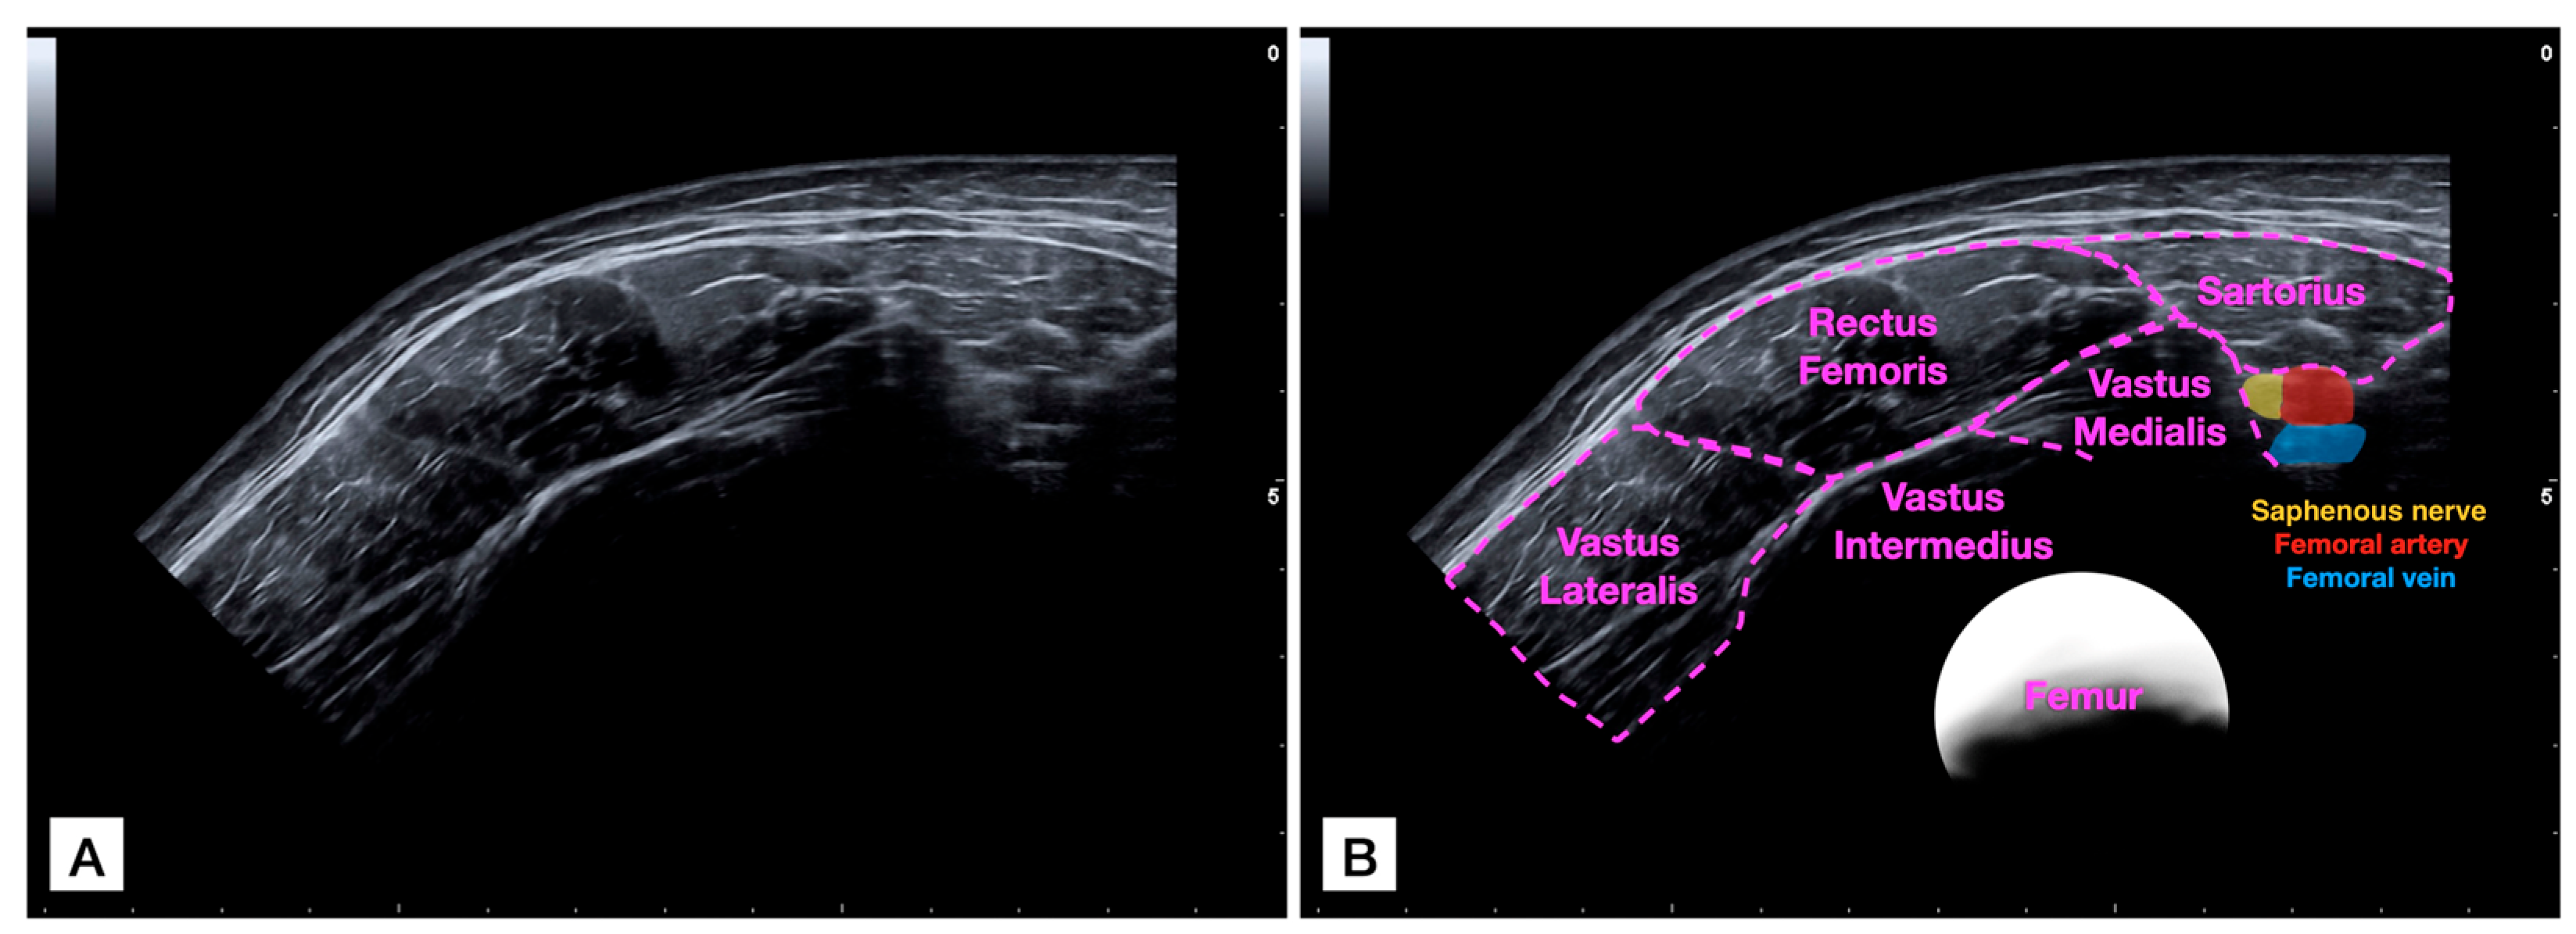

2.3. Panoramic Ultrasound Imaging Capture